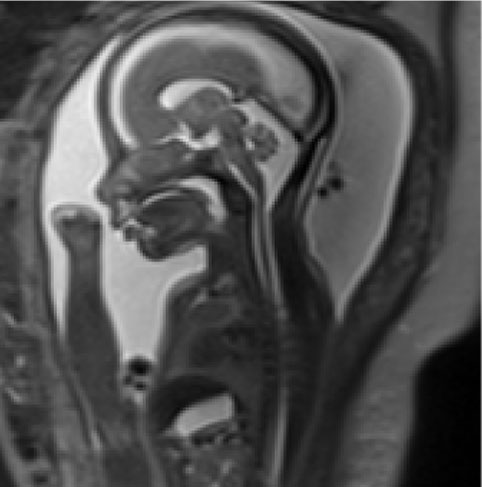

FETAL MRI

A fetal MRI is used as an additional tool for advanced evaluation of structural abnormalities especially involving the fetal brain, bowel, head/neck tumours, spine, lungs and placenta. It has been proven to be safe for use in the 2nd and 3rd trimester of pregnancy and has no radiation exposure.

We are the only centre in Gujarat and among the few in India to provide expert MRI scans of a fetus with an experience of more than 10 years.

A fetal MRI is a specialized imaging test that may be helpful in evaluating your fetus for congenital anomalies and associated complications.  Like an ultrasound, an MRI does not use the type of radiation that can cause DNA damage, so we believe it is safe to perform in pregnancy